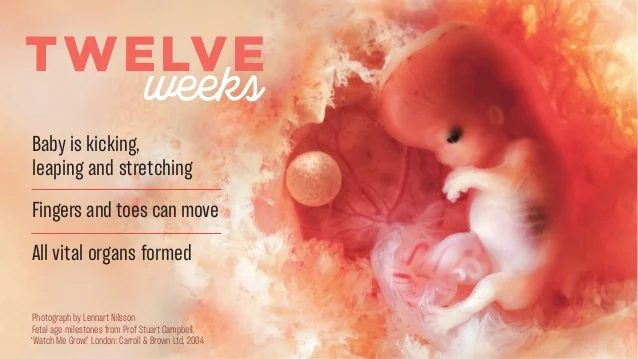

Работы знаменитого фотографа Леннарта Нильссона

Раздел: Фотопанорама